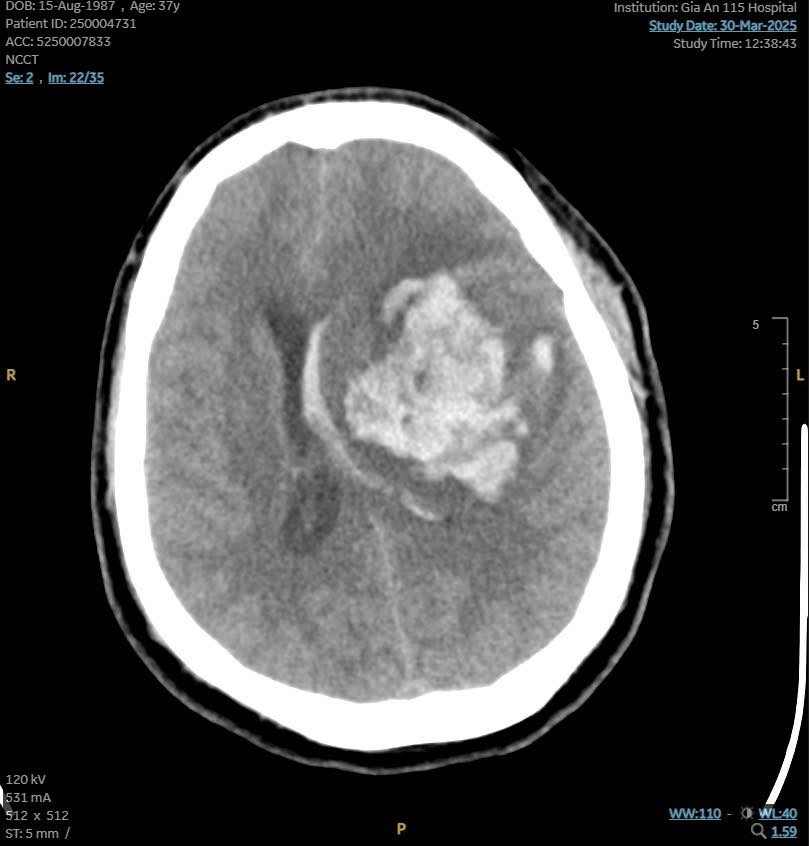

Sau khi cấp cứu hồi sinh tim phổi tích cực, tim bệnh nhân đập trở lại và được chuyển đến bệnh viện. Tại đây, kết quả CT scan cho thấy bệnh nhân bị xuất huyết não lan rộng gần hết bán cầu não trái, tràn vào não thất, gây phù não và đẩy lệch đường giữa, BS Nhật Tuệ cho biết.

Hình ảnh CT scan của bệnh nhân cho thấy tình trạng phù não và đẩy lệch đường giữa (Ảnh: BVCC)